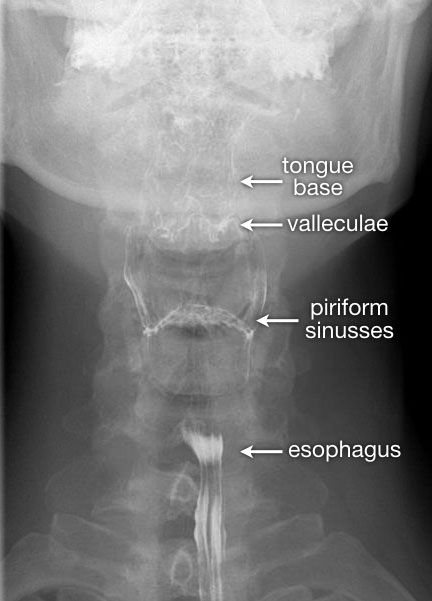

Tư thế thẳng (AP-view) quan trọng để đánh giá sự bất đối xứng.

Sau khi hoàn thành chuỗi hình ảnh giai đoạn hầu họng, cần theo dõi bolus thuốc cản quang toàn bộ đường đi xuống đến chỗ nối thực quản-dạ dày.

TRÁI: Tư thế nghiêng khi bệnh nhân phát âm “aaa”. Xương móng (H) và nền lưỡi (T) di chuyển ra trước. Xoang hình lê trái và phải được chiếu chồng lên nhau. Đầu mút của màn hầu (SP) được quan sát thấy. PHẢI: Các hố lưỡi-thanh thiệt (V) và xoang hình lê (P).

Hình ảnh đối quang kép của hầu họng

Đối với tư thế nghiêng, yêu cầu bệnh nhân phát âm “aaa”, vì điều này sẽ đưa lưỡi về phía trước và cho phép quan sát tốt hơn vùng hầu miệng và hạ hầu.

Trong tiếng Hà Lan, đây là chữ “eee”, vì được phát âm tương tự như “aaa” trong tiếng Anh.

Đối với tư thế AP, nghiệm pháp Valsalva cải tiến được thực hiện.

Bệnh nhân phải thổi hơi qua môi mím chặt như khi thổi kèn trumpet, đồng thời thư giãn vùng cổ.

Luôn thực hành nghiệm pháp này trước khi thăm khám để bệnh nhân biết cách thực hiện.

Bên trái là hình ảnh đối quang kép của hầu họng.

Sự phồng ra của thành bên hầu họng là bình thường và có thể khá rõ rệt (như trường hợp Dizzy Gillespie).

Những cấu trúc này được gọi là ‘tai hầu bên’ (lateral pharyngeal ears).